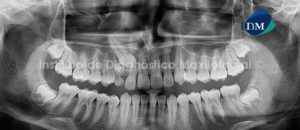

010 – Osteonecrosis

Paciente de sexo femenino y de 38 años de edad, es referida al Instituto de Diagnóstico Maxilofacial para la evaluación de un proceso infeccioso en el lado derecho del maxilar inferior.